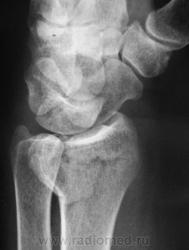

Катенёв Валенти... Дата публикации 12.01.2010, 17:50 Случай 1. Пациент направлен хирургом на рентгенографию лучезапястного сустава. Втр, 12/01/2010 - 18:02 #1 Катенёв Валенти... Не на сайте Был на сайте: 7 лет 3 недели назад Зарегистрирован: 22.03.2008 - 22:15 Публикации: 54876 Случай 2. Пациент направлен на рентгенографию лучезапястного сустава. Comment Upload: Втр, 12/01/2010 - 18:09 #2 Катенёв Валенти... Не на сайте Был на сайте: 7 лет 3 недели назад Зарегистрирован: 22.03.2008 - 22:15 Публикации: 54876 Случай 3. Пациент направлен на рентгенографию плечевого сустава. Comment Upload: Ср, 13/01/2010 - 17:31 #3 Ольга Дмитриевна Не на сайте Был на сайте: 15 лет 9 месяцев назад Зарегистрирован: 13.01.2010 - 16:55 Публикации: 168 По поводу случая 1. С лучом все понятно, а вот переломовывих ладьевидной кости? Как думаете? Красота - гормон карьерного роста! Ср, 13/01/2010 - 22:53 #4 Катенёв Валенти... Не на сайте Был на сайте: 7 лет 3 недели назад Зарегистрирован: 22.03.2008 - 22:15 Публикации: 54876 А вот как трактовать в случае 2 перелом? Ср, 13/01/2010 - 23:47 #5 Ольга Дмитриевна Не на сайте Был на сайте: 15 лет 9 месяцев назад Зарегистрирован: 13.01.2010 - 16:55 Публикации: 168 В случае 2 - на мой взгляд внутрисуставной перелом задненаружного края дист эпифиза лучевой кости. Что за +ткань по нар краю эпифиза луча - сложно сказать, мож ломал раньше. Красота - гормон карьерного роста! Ср, 13/01/2010 - 23:48 #6 Ольга Дмитриевна Не на сайте Был на сайте: 15 лет 9 месяцев назад Зарегистрирован: 13.01.2010 - 16:55 Публикации: 168 Что скажете по поводу случая1? Красота - гормон карьерного роста! Чт, 14/01/2010 - 18:17 #7 Глазков Игорь А... Не на сайте Был на сайте: 9 месяцев 2 недели назад Зарегистрирован: 19.12.2008 - 20:41 Публикации: 1597 оскольчатый перелом лучевой кости. Прийди к Себе Пт, 15/01/2010 - 22:26 #8 Катенёв Валенти... Не на сайте Был на сайте: 7 лет 3 недели назад Зарегистрирован: 22.03.2008 - 22:15 Публикации: 54876 "Красиво" упал. "Красивый" перелом Comment Upload: Вс, 17/01/2010 - 09:48 #9 Катенёв Валенти... Не на сайте Был на сайте: 7 лет 3 недели назад Зарегистрирован: 22.03.2008 - 22:15 Публикации: 54876 Случай 5. Comment Upload:

По поводу случая 1. С лучом все понятно, а вот переломовывих ладьевидной кости? Как думаете?

Что скажете по поводу случая1?

оскольчатый перелом лучевой кости.